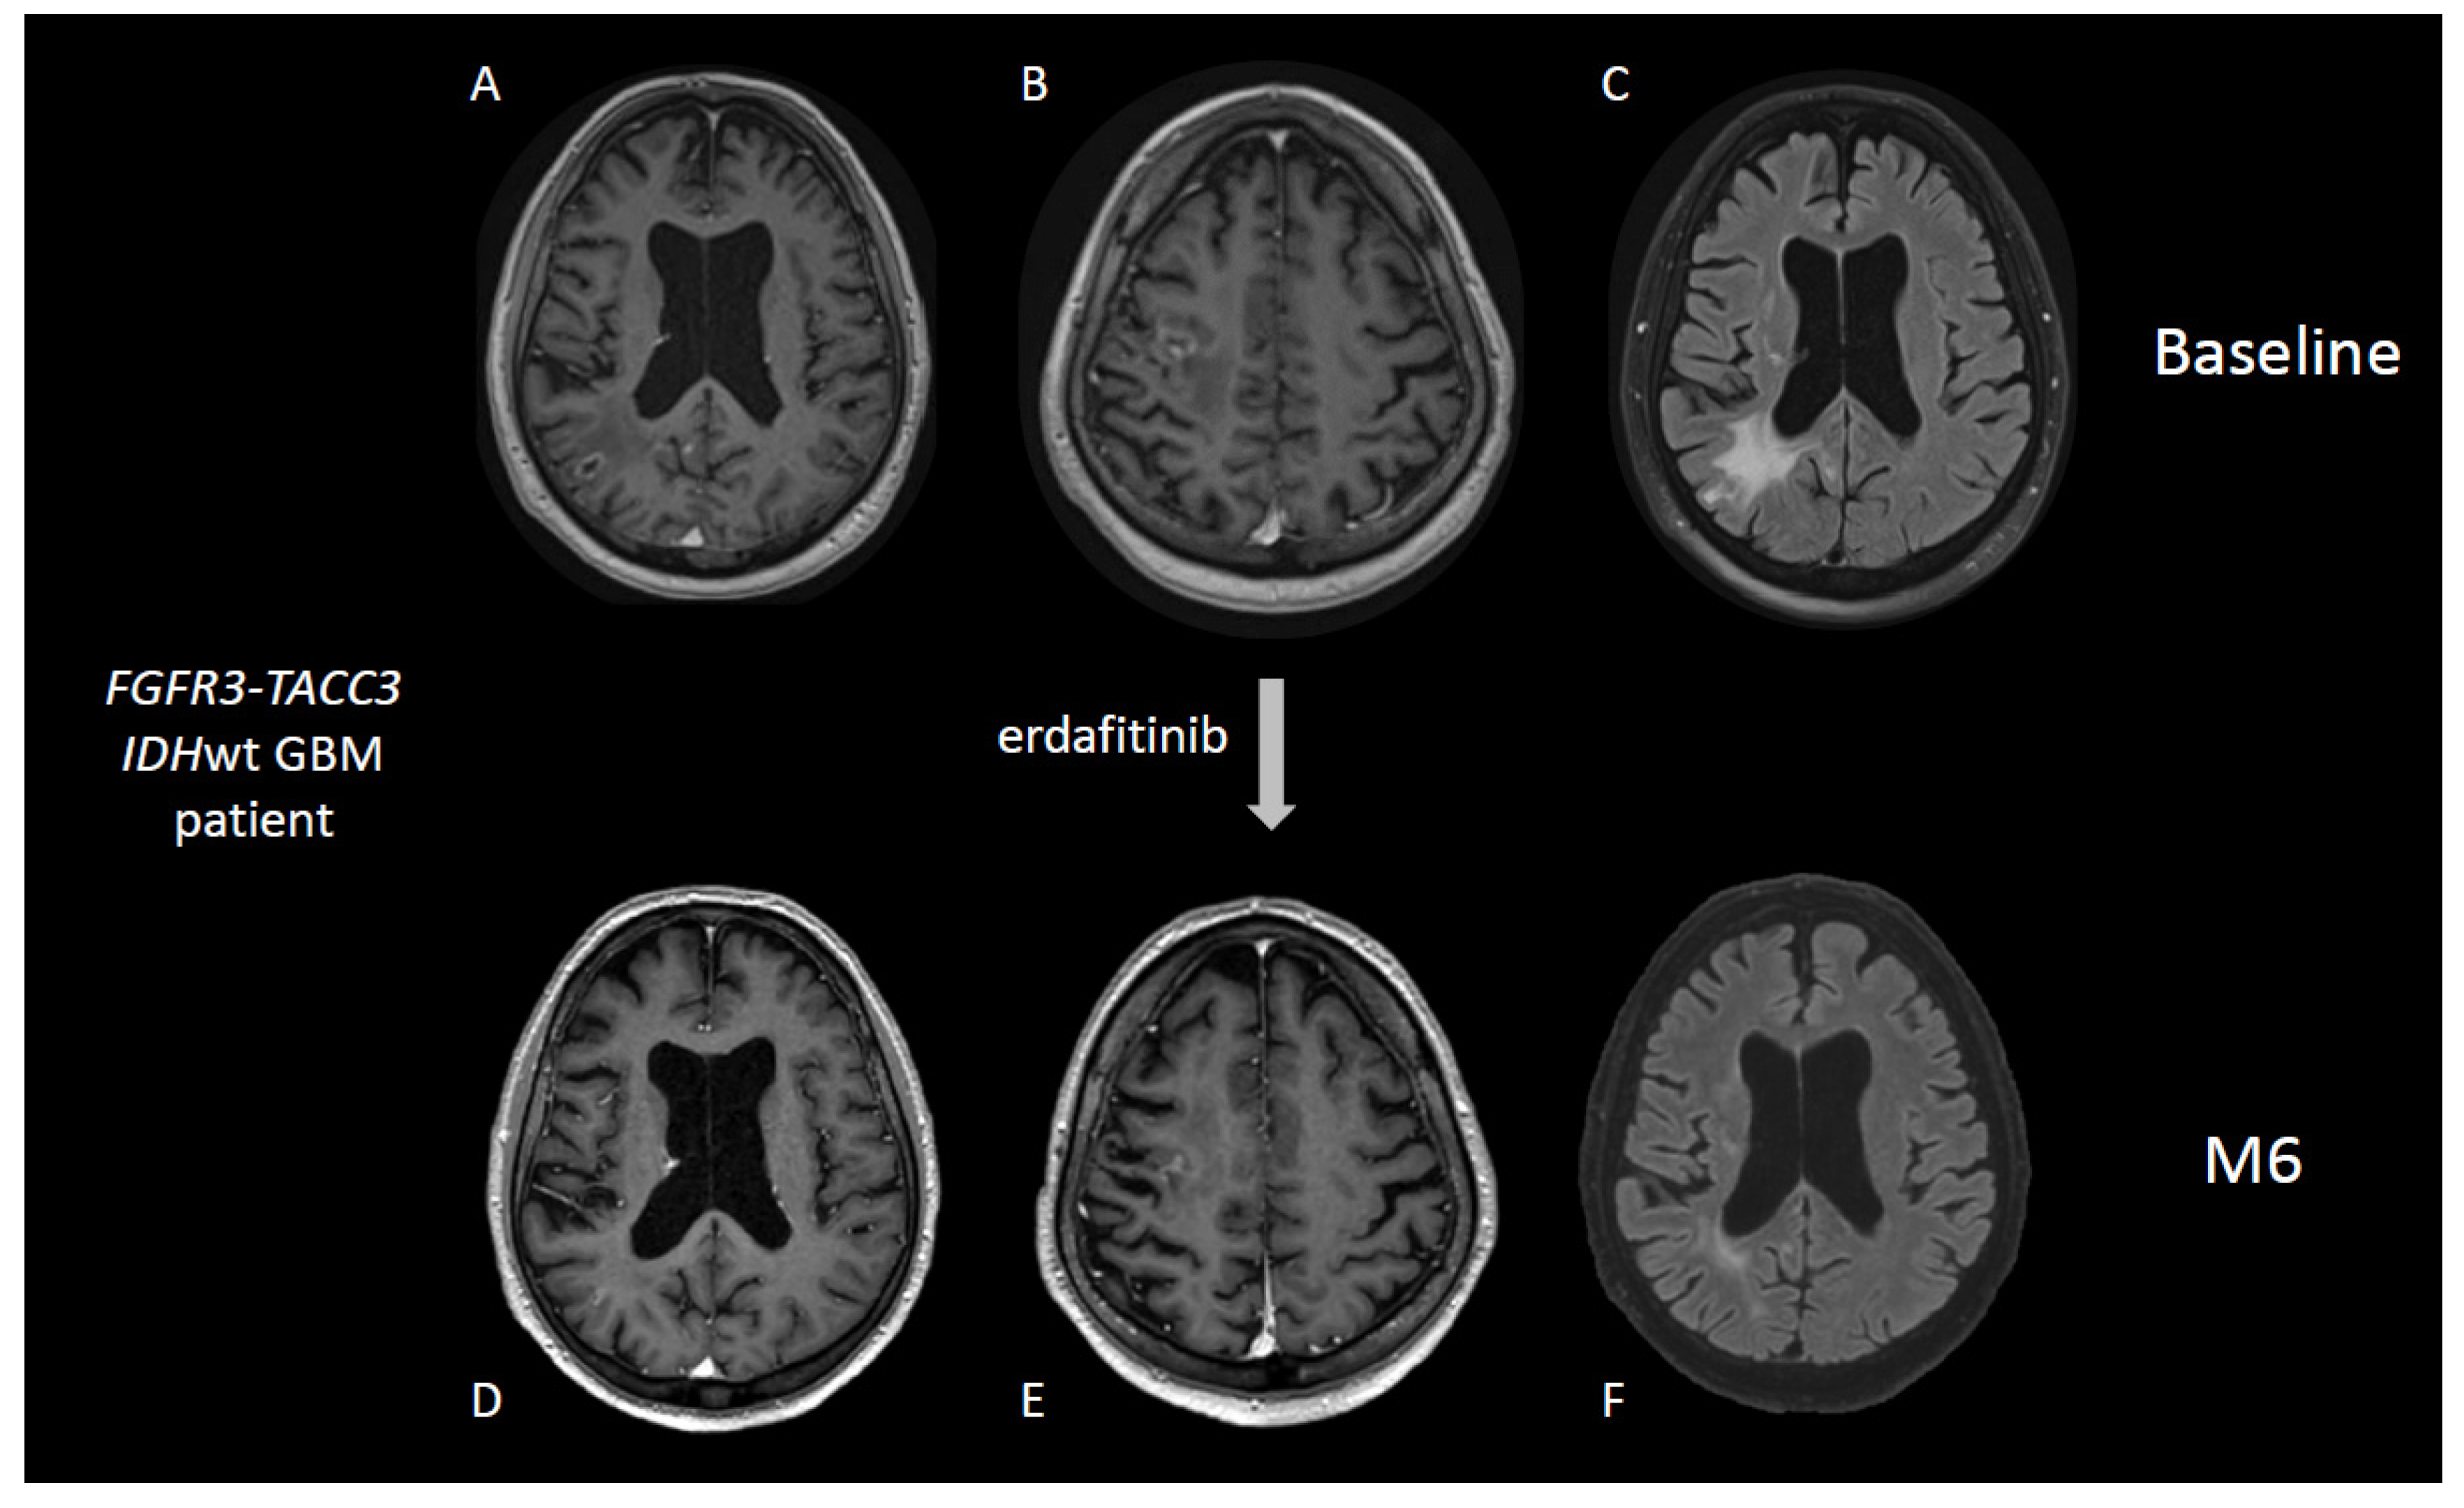

5.3. Inhibition of FGFR3-TACC3 Gene Fusions and Activating Mutations of FGFR1 Gene

- Di Stefano, A.L.; Picca, A.; Saragoussi, E.; Bielle, F.; Ducray, F.; Villa, C.; Eoli, M.; Paterra, R.; Bellu, L.; Mathon, B.; et al. Clinical, Molecular, and Radiomic Profile of Gliomas with FGFR3-TACC3 Fusions. Neuro-Oncology 2020, 22, 1614–1624. [Google Scholar] [CrossRef]

- Di Stefano, A.L.; Fucci, A.; Frattini, V.; Labussiere, M.; Mokhtari, K.; Zoppoli, P.; Marie, Y.; Bruno, A.; Boisselier, B.; Giry, M.; et al. Detection, Characterization, and Inhibition of FGFR-TACC Fusions in IDH Wild-Type Glioma. Clin. Cancer Res. 2015, 21, 3307–3317. [Google Scholar] [CrossRef] [Green Version]